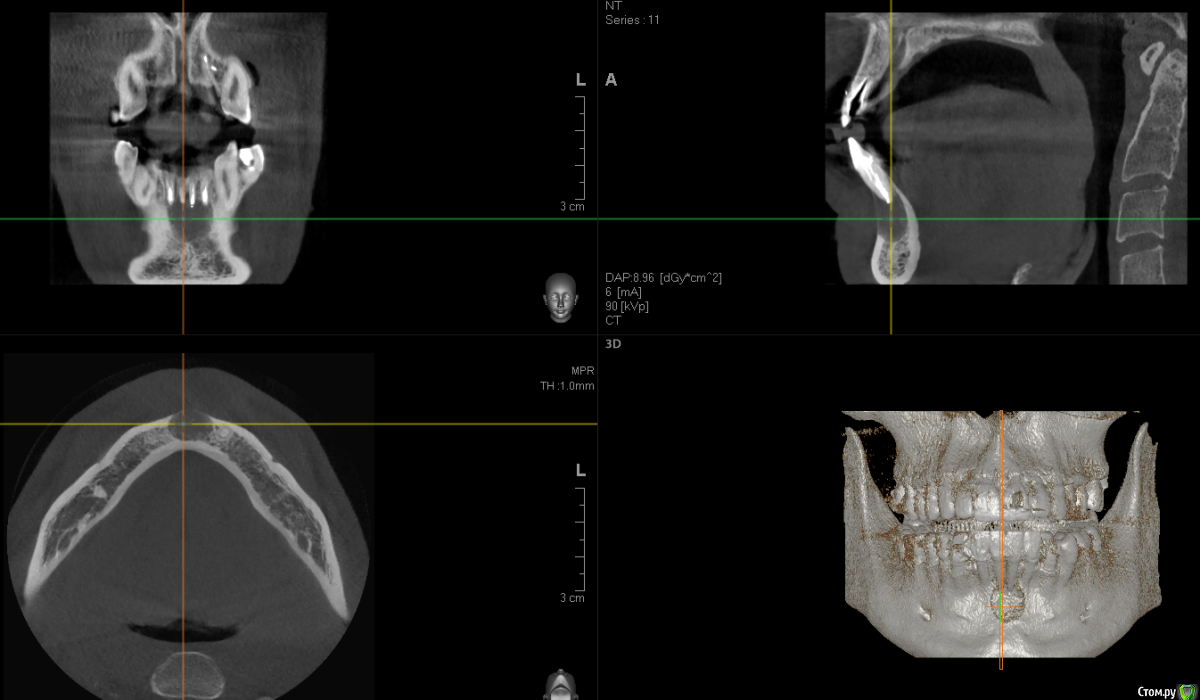

dirkdigglerdirk Опубликовано 24 августа, 2017 Поделиться Опубликовано 24 августа, 2017 Здравствуйте, уважаемые стоматологи. Пожалуйста, прокомментируйте мою ситуацию. Киста впервые обнаружена около 4 лет назад, появилась боль при накусывании, открывались гнойные свищи в области центральных резцов. Были пролечены каналы с закладкой лекарства калосепт, в результате достигнута положительная динамика (уменьшение кисты). Затем через 4 года киста вновь воспалилась - на данный момент ситуация такая как на снимках (снимки свежие). Зубы на данный момент не болят, последний раз свищ открывался около 4 месяцев назад. Зубы под коронками - три под временными (поставили недавно, с перспективой замены на постоянные после операции и наблюдения), один под постоянной коронкой со вкладкой. Каналы в трех зубах перелечены в июне с закладкой лекарства калосепт. Врачом запланирована операция цистэктомия с резекцией верхушек корней 4 зубов, возможно с ретроградной пломбировкой каналов и с закладкой костных гранул в полость. Скажите, каковы варианты лечения? Каковы перспективы сохранить эти зубы? Как бы действовали вы? Интересно ваше мнение, спасибо. Если требуется, могу выложить КТ полностью. Ссылка на комментарий